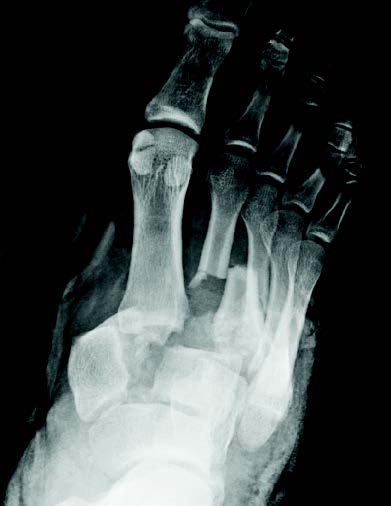

- Primary Objective Observational study comparing outcomes following limb salvage versus amputation of a severe distal tibia, ankle, and/or foot trauma